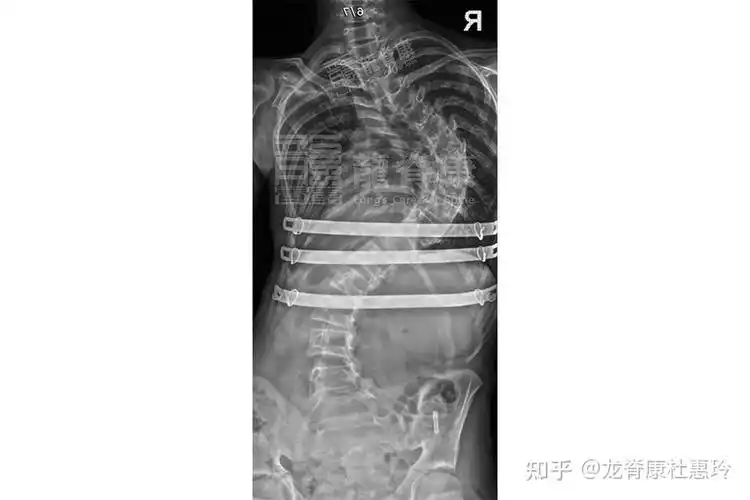

(漏斗胸引起的脊柱侧弯和胸廓畸形,建议胸廓成型术,图为胸廓成形术术